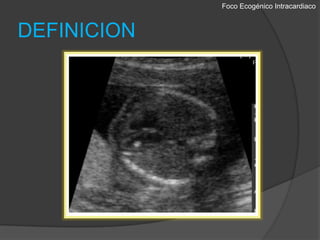

Foco EcogénicoIntracardiacoDEFINICIONEl foco ecogenicointracardicos se describe como áreas de  ecogenicidadcomparable a la del hueso, en la región de los músculos papilares en cualquiera de los ventrículos. 1-288% en el ventrículo izquierdo, el 5% en el derecho, y el 7% biventricular. 3Se encuentran del 1,5 al 4% de los embarazos normales.Obstetricia Integral Siglo XXI. Universidad Nacional, Facultad de Medicina, Departamento de Obstetricia y GinecologiaDiagnostico Prenatal con Ultrasonido. Jaime Arenas Gamboa, Javier Andrés Ramírez Martínez.

Foco EcogénicoIntracardiacoDEFINICIONUtilizando un transductor de frecuencia apropiada (5 MHz) y ajustando la ganancia, el foco ecogénico debe visualizarse en la vista estandar de cuatro camaras en un estudio ecográfico habitual.El foco debe ser visto desde varios angulos para asegurarse de que no corresponde con reflexiones especulares de los musculos papilares.Obstetricia Integral Siglo XXI. Universidad Nacional, Facultad de Medicina, Departamento de Obstetricia y GinecologiaDiagnostico Prenatal con Ultrasonido. Jaime Arenas Gamboa, Javier Andrés Ramírez Martínez.

Foco EcogénicoIntracardiacoDEFINICIONEl focoecogenicointracardicos se describe como áreas de ecogenicidadcomparable a la del hueso, en la región de los músculos papilares en cualquiera de los ventrículos. 1-288% en el ventrículo izquierdo, el 5% en el derecho, y el 7% biventricular. 3Se encuentran del 1,5 al 4% de los embarazos normales.Obstetricia Integral Siglo XXI. Universidad Nacional, Facultad de Medicina, Departamento de Obstetricia y GinecologiaDiagnostico Prenatal con Ultrasonido. Jaime Arenas Gamboa, Javier Andrés Ramírez Martínez.

Foco EcogénicoIntracardiacoDEFINICIONUtilizando un transductorde frecuencia apropiada (5 MHz) y ajustando la ganancia, el foco ecogénico debe visualizarse en la vista estandar de cuatro camaras en un estudio ecográfico habitual.El foco debe ser visto desde varios angulos para asegurarse de que no corresponde con reflexiones especulares de los musculos papilares.Obstetricia Integral Siglo XXI. Universidad Nacional, Facultad de Medicina, Departamento de Obstetricia y GinecologiaDiagnostico Prenatal con Ultrasonido. Jaime Arenas Gamboa, Javier Andrés Ramírez Martínez.